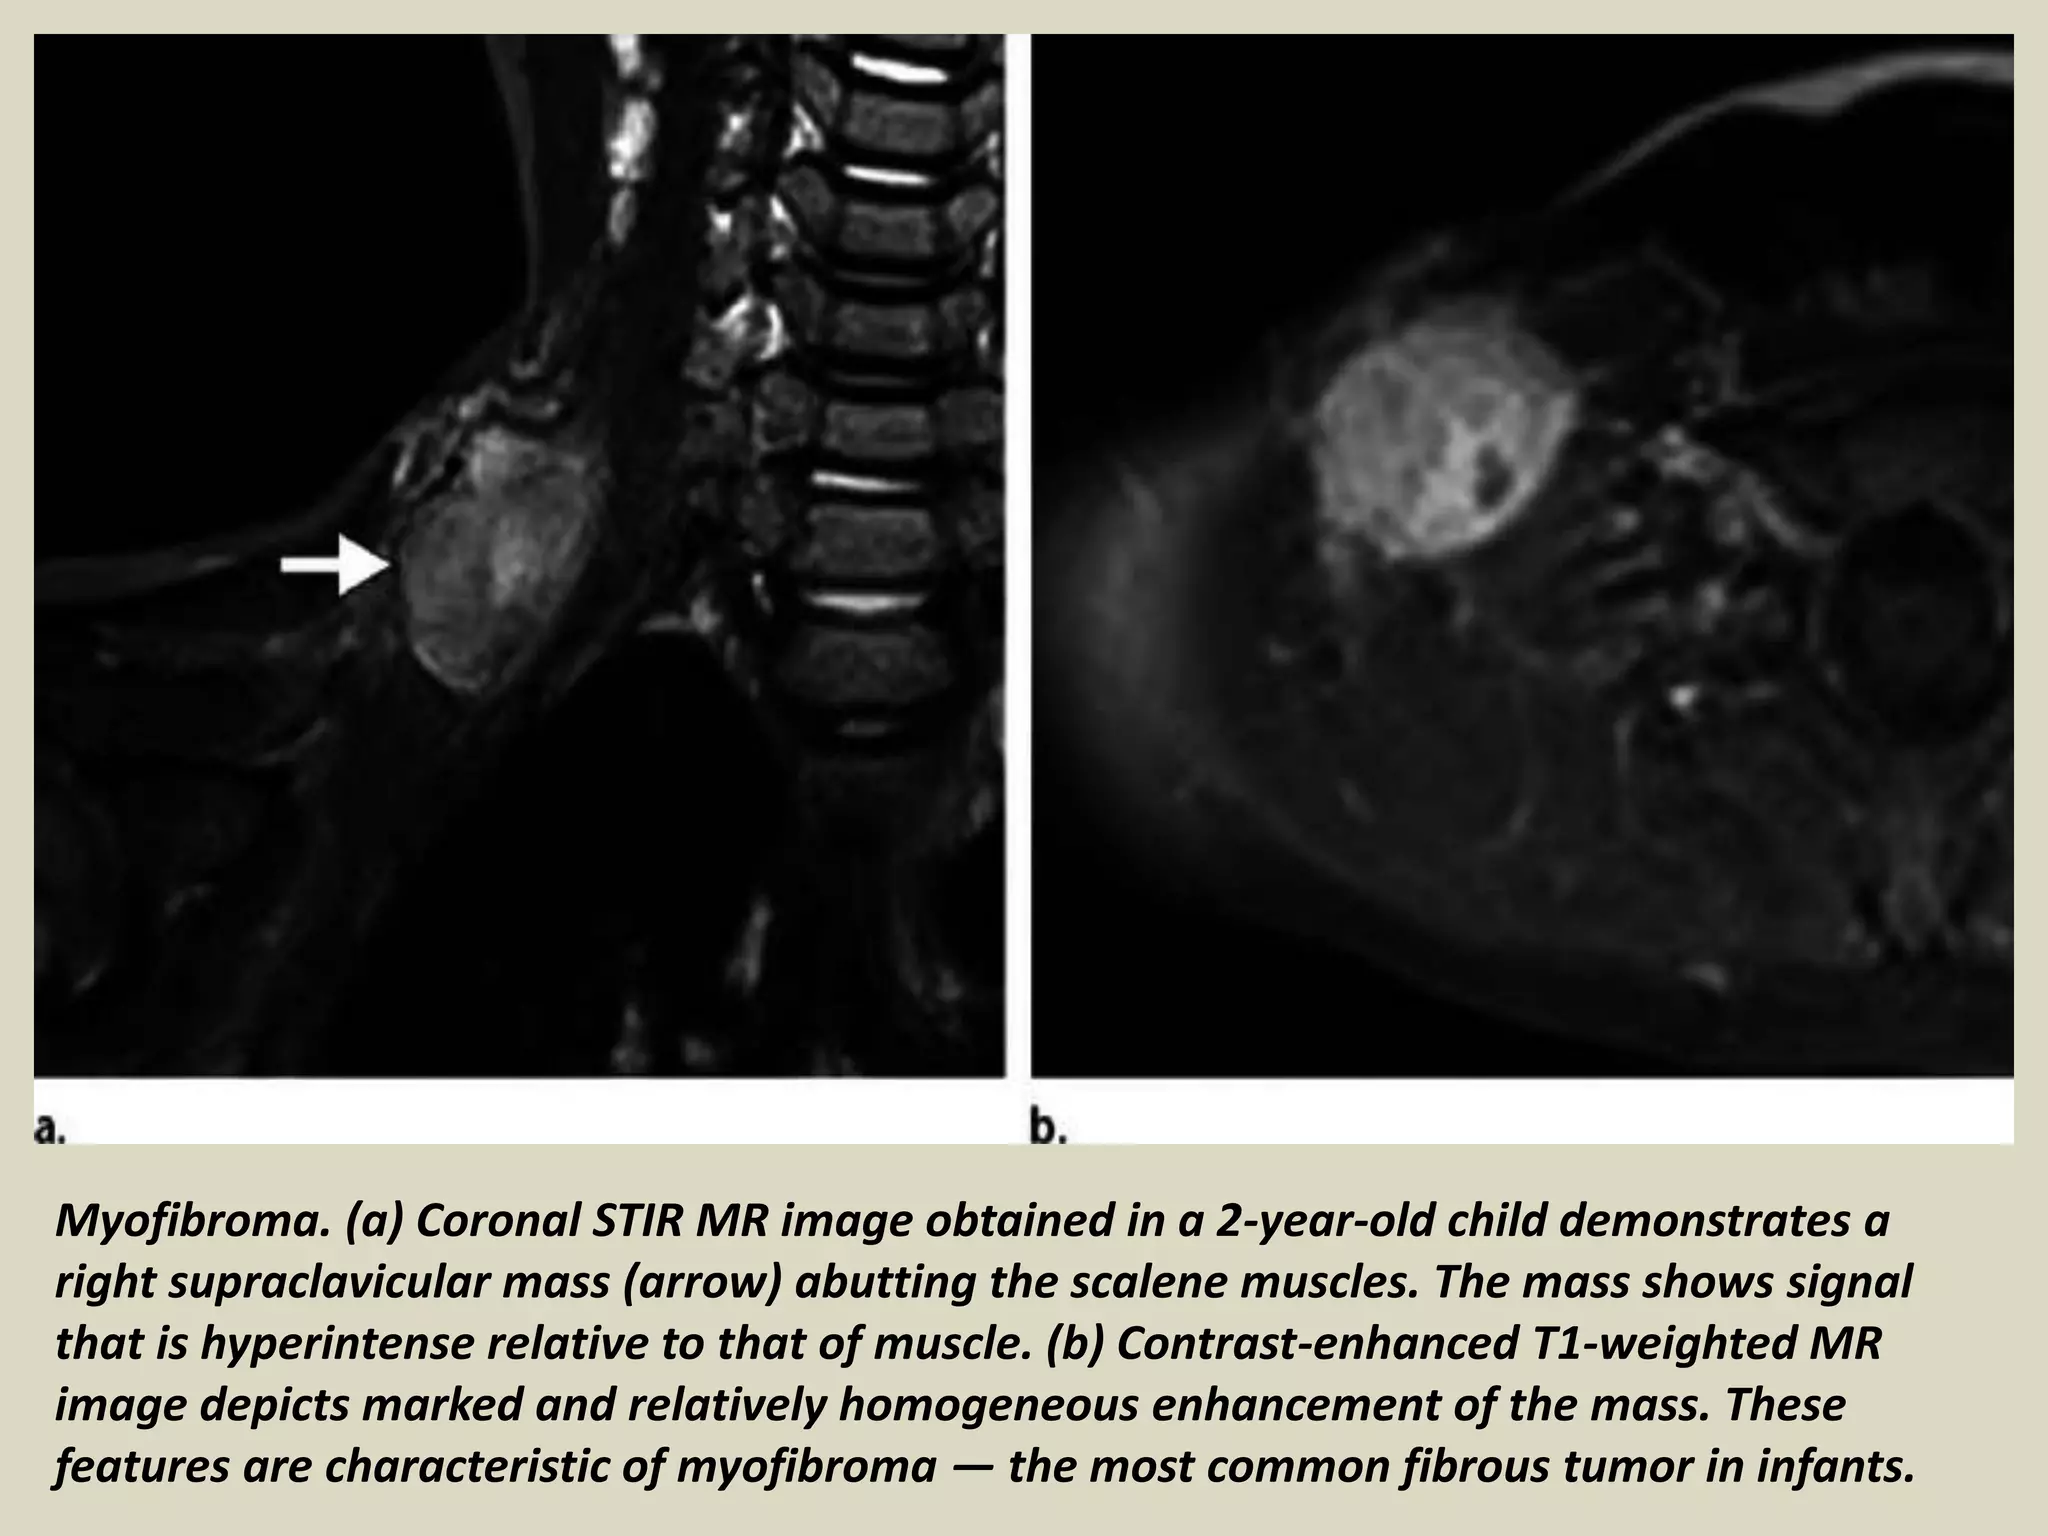

Myofibroma. (a) Coronal STIR MR image obtained in a 2-year-old child demonstrates a

right supraclavicular mass (arrow) abutting the scalene muscles. The mass shows signal

that is hyperintense relative to that of muscle. (b) Contrast-enhanced T1-weighted MR

image depicts marked and relatively homogeneous enhancement of the mass. These

features are characteristic of myofibroma — the most common fibrous tumor in infants.